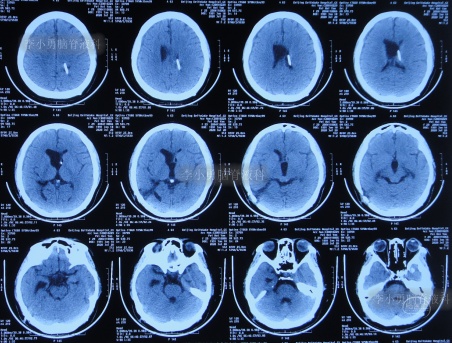

于入院后2019年12月30日,进行了第3次进行了脑室腹腔分流术(分流阀初始压力2.0),仍保留了原2根脑室分流管;术后当天查头颅CT示脑室仍有扩张,脑室内有3根管(图-9)。

图-9:2019年12月30日头颅CT

第3次脑室腹腔分流术后1个月即2020年2月初,再次出现记忆力减退视物模糊,再过1个月仍无任何改善,于2020年3月17日(第3次脑室腹腔分流术后2个半月),到江苏省江阴某医院检查了头颅CT示脑室仍扩张(图-10)。

图-10:2020年3月17日头颅CT

2020年4月5日(第1次调压后18天),因症状持续不见减轻,到江苏省江阴某医院查头颅CT示脑室仍扩张(图-11)。

图-11:2020年4月5日头颅CT

但第2次调压仅2天后,症状又加重,到江苏省江阴某医院查头颅CT示脑室仍扩张(图-12)。为求进一步有效治疗,通过网络找到北京的李小勇脑脊液科。

图-12:2020年4月9日头颅CT

脑积水第1次脑室腹腔分流术后14年,即第2次脑室腹腔分流术后13年,即第3次脑室腹腔分流术后3个月半,5次就诊于给予手术的医院但仍脑积水,颅内感染情况下于2020年4月11日,住入李小勇脑脊液科,入院时:头晕伴视物不清,呕吐,睡眠差,头部有手术瘢痕(图-13);入院时头颅CT示脑积水,脑室内有3根管(图-14)。

图-14:2020年4月11日入院时头颅CT

入院后4天即2020年4月15日,拔除了原3根分流管+两侧脑室外引流术(图-15)。

图-15:2020年4月15日头颅CT

图-16:2020年4月16日头颅CT